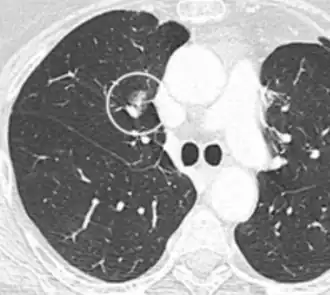

- Margin morphology: a spiculated margin is a risk factor for cancer.[8] Benign causes tend to have a well defined border, whereas lobulated lesions or those with an irregular margin extending into the neighbouring tissue tend to be malignant.[10] In particular, spiculations are highly predictive of malignancy with a positive predictive value up to 90%.[9] Also, a "notch sign", which is an abrupt indentation of the nodule, increases the risk of cancer, but may also be found in granulomatous diseases.[9]

-

subpleural nodule.[9] -

Round well-delineated solid lung nodule with smooth border.[9] -

Lobulated nodule.[9] -

Spiculated lung nodule.[9] -

A "notch sign".[9] -

A triangular perifissural node can be diagnosed as a benign lymph node.[9]